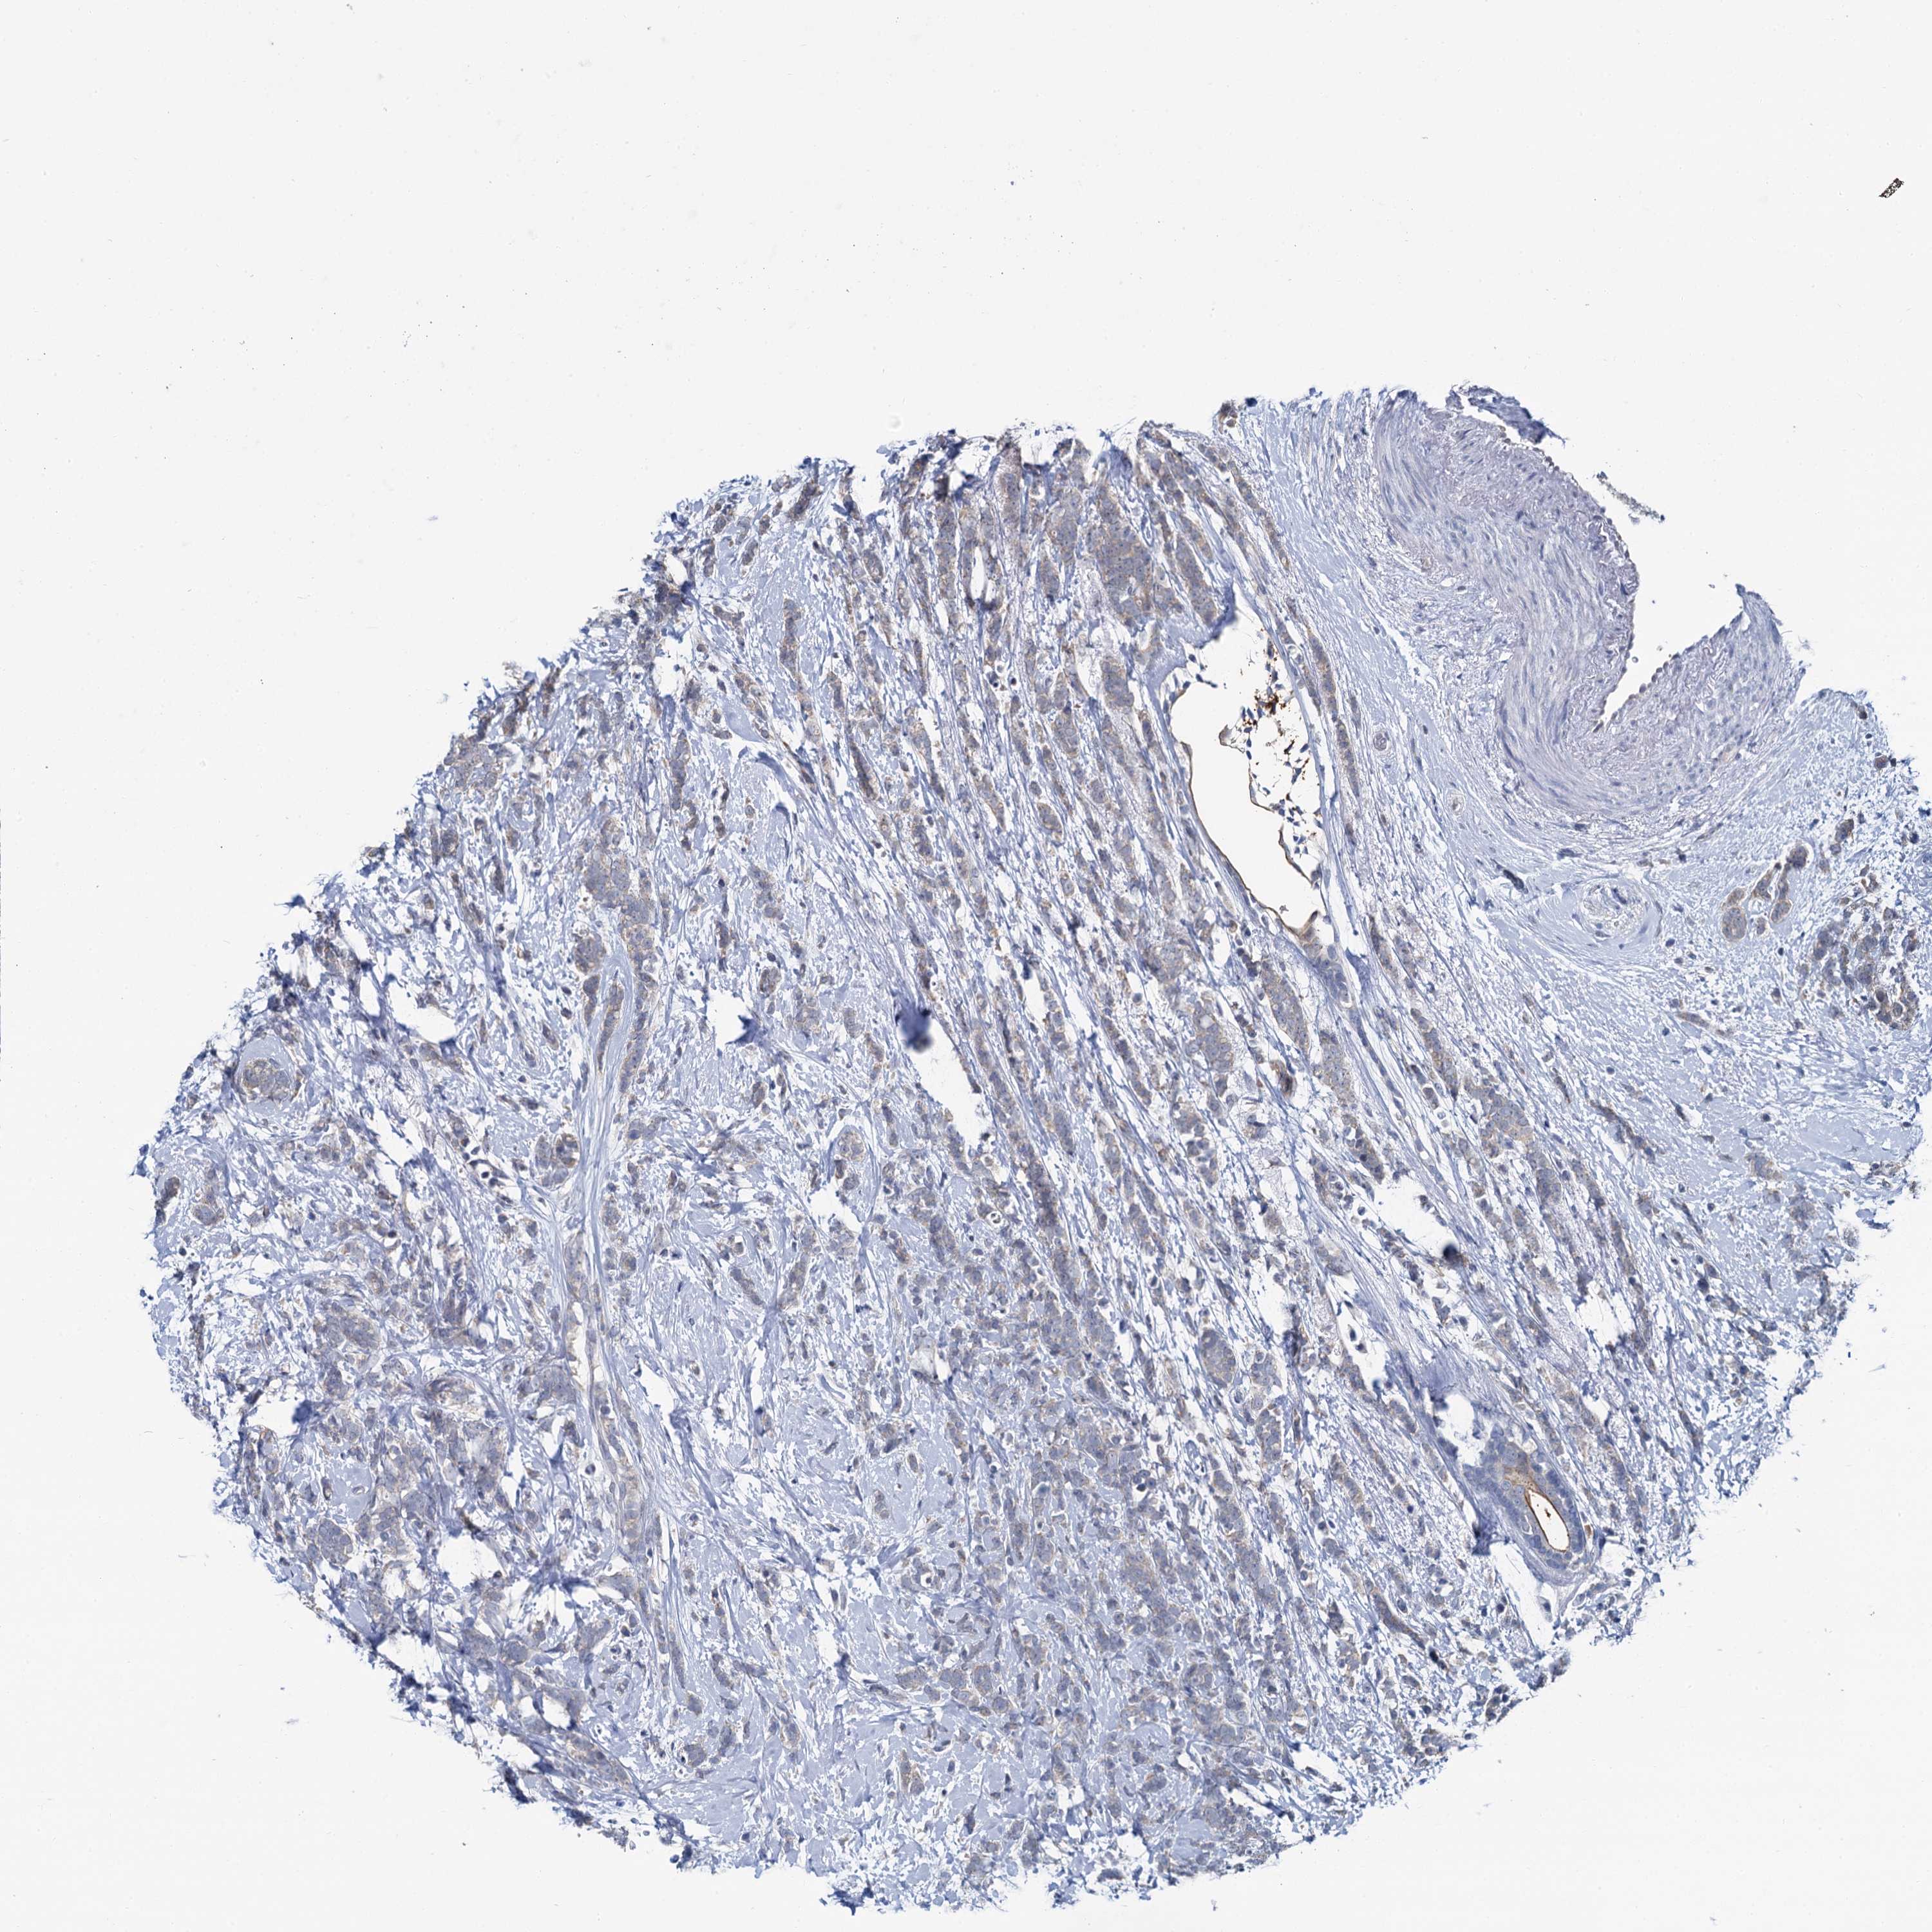

CANCER BREAST CANCER Show tissue menu

BRCA TCGA BRCA VALIDATION PROTEIN EXPRESSION